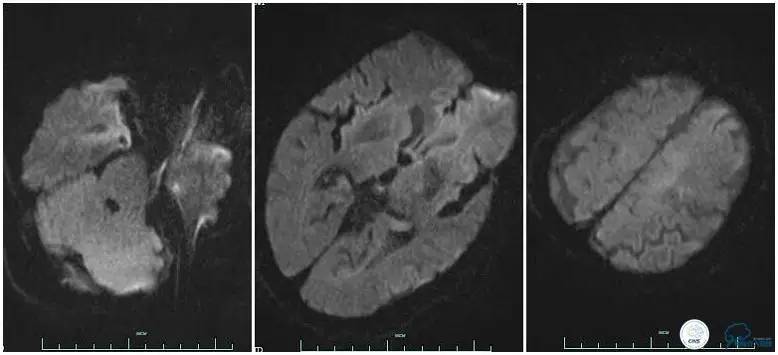

术前头颅MRA。

12:35穿刺成功,TOT 185min。3型主动脉弓,右侧颈内动脉起始部狭窄70%,右侧大脑前动脉A1段未显影。

双侧大脑前动脉A4段闭塞,右侧大脑前动脉由左侧大脑前动脉经前交通动脉代偿供血。